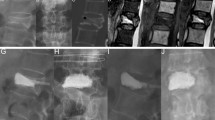

The results (Table 5) of corresponding analysis on VAS, vertebral height and Cobb angle in patients with poor efficacy showed that postoperative VAS was positively correlated with preoperative vertebral height (r = 0.872, p < 0.01) (Fig. 1), and was also positively correlated with postoperative Cobb angle (r = 0.820, p < 0.01) (Fig. 2) and the Cobb angle in postoperative 1 year (r = 0.717, p < 0.01) (Fig. 2). It was suggested that vertebral height, postoperative Cobb angle and the Cobb angle in postoperative 1 year as well as the postoperative VAS had an increasing trend. There was also a positive correlation between the VAS value and the Cobb angle in 1 year after surgery (r = 0.689, p < 0.01) (Fig. 3). In addition, the correlations between preoperative vertebral height and postoperative Cobb angle (r = 0.770, p < 0.01), between preoperative vertebral height and the vertebral height in postoperative 1 year (r = 0.851, p < 0.01), and between postoperative Cobb angle and the Cobb angle in postoperative 1 year, were also very significant.

According to the results in Table 5, it could be seen that VAS, height of injured vertebra and the change in Cobb angle are correlated in patients demonstrating poor curative effect. Figures 1 and 2 show that postoperative VAS is positively correlated with preoperative vertebral height, postoperative Cobb angle and Cobb angle 1 year after surgery, suggesting that the higher preoperative vertebral height, postoperative Cobb angle and Cobb angle 1 year after surgery, the higher postoperative VAS. Figure 3 show that VAS value 1 year after surgery is positively correlated with cobb value 1 year after surgery. In addition, the correlation between preoperative vertebral height and postoperative cobb, postoperative vertebral height and vertebral height 1 year after surgery, postoperative cobb and cobb 1 year after surgery is also significant. The mechanism of this situation is currently unclear. It may be related to the change in spinal curvature after PKP surgery. Jin38 et al. believe that: It can be concluded that proper correction of kyphosis deformity and restoration of vertebral height can restore normal spinal physiological curvature; however, higher correction angle and correction height are not necessarily better, and further biomechanical studies and clinical studies are needed for determining the degree of recovery involving kyphosis angle and vertebral height. Some scholars hold that vertebroplasty increases the risk of recurrent fractures of adjacent vertebral bodies39. As for the related factors of adjacent vertebral fractures, studies find that the stiffness of the vertebral body rises and the degeneration of intervertebral disc accelerates after injecting bone cement into the vertebral body when performing PVP or PKP, especially when the bone cement leaks into the intervertebral disc where the risk of adjacent vertebral fractures increases40,41; however, it is found in a prospective multicenter randomized controlled study led by Klazen42 that intervertebral disc leakage is not correlated with the incidence rate of adjacent vertebral refracture. Clinical studies reveal that refractures of adjacent vertebral bodies are related to bone mineral density index and kyphosis angle, and the recovery degree of kyphosis angle is positively correlated with the incidence rate of refractures of adjacent vertebral bodies, stressing that excessive recovery of vertebral height and kyphosis angle in surgery is inadvisable. Since the recovery of vertebral height is positively correlated with the volume of bone cement injection, it remains unclear whether the risk of this new vertebral fracture is caused by recovery of vertebral height, or secondary effect due to increased volume of bone cement injection43. Mu44 et al. consider that, by comparing with ordinary-viscosity bone cement, vertebroplasty of high-viscosity bone cement features more advantages in spinal function recovery, physiological structure and leakage reduction. How changes in spinal curvature after PKP and recovery of vertebral height correlate with postoperative outcomes requires further research in the future.